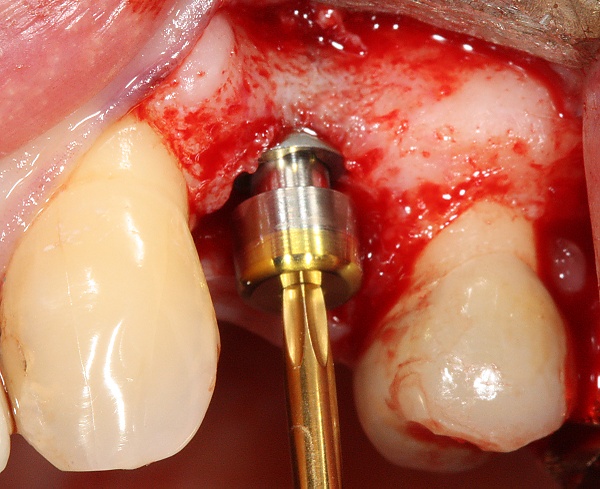

Разборный имплантат состоит из непосредственно имплантата и надстройки (супраструктуры), именуемой абатментом. Такой имплантат может быть установлен по одно- и двухэтапному протоколу. Двухэтапный протокол подразумевает полное погружение имплантата и накрывание его слизистой оболочкой, в результате чего исключается любой контакт имплантата с полостью рта — эта процедура называется первым этапом дентальной имплантации. Второй этап заключается в установке какой-либо надстройки (супраструктуры) — это может быть как формирователь десны, так и абатмент с временной коронкой или другим видом протезной конструкции. После какого промежутка времени будет выполнен второй этап обычно решает имплантолог, опираясь на данные о качестве костной ткани, возраст и общее состояние пациента, а также свой клинический опыт. Классические сроки составляют 4—6 месяцев, однако последнее время существует тенденция к сокращению сроков ожидания до 2,5—3 месяцев. Это связано с лучшим пониманием процесса остеоинтеграции, а также оптимизацией макродизайна и микрохарактеристик поверхности имплантатов.

В неразборном имплантате (употребляются также термины: одноэтапный имплантат, моноимплантат) внутрикостная часть имплантата и абатмент обычно изготовлены из единого куска материала. После установки имплантат своей наддесневой частью сразу оказываются в контакте с полостью рта. На усмотрение доктора устанавливается формирователь десны либо временная коронка. В случае установки временной протезной конструкции (коронки, моста или полного протеза) на имплантат не позднее трёх дней после имплантации говорят о немедленной нагрузке.